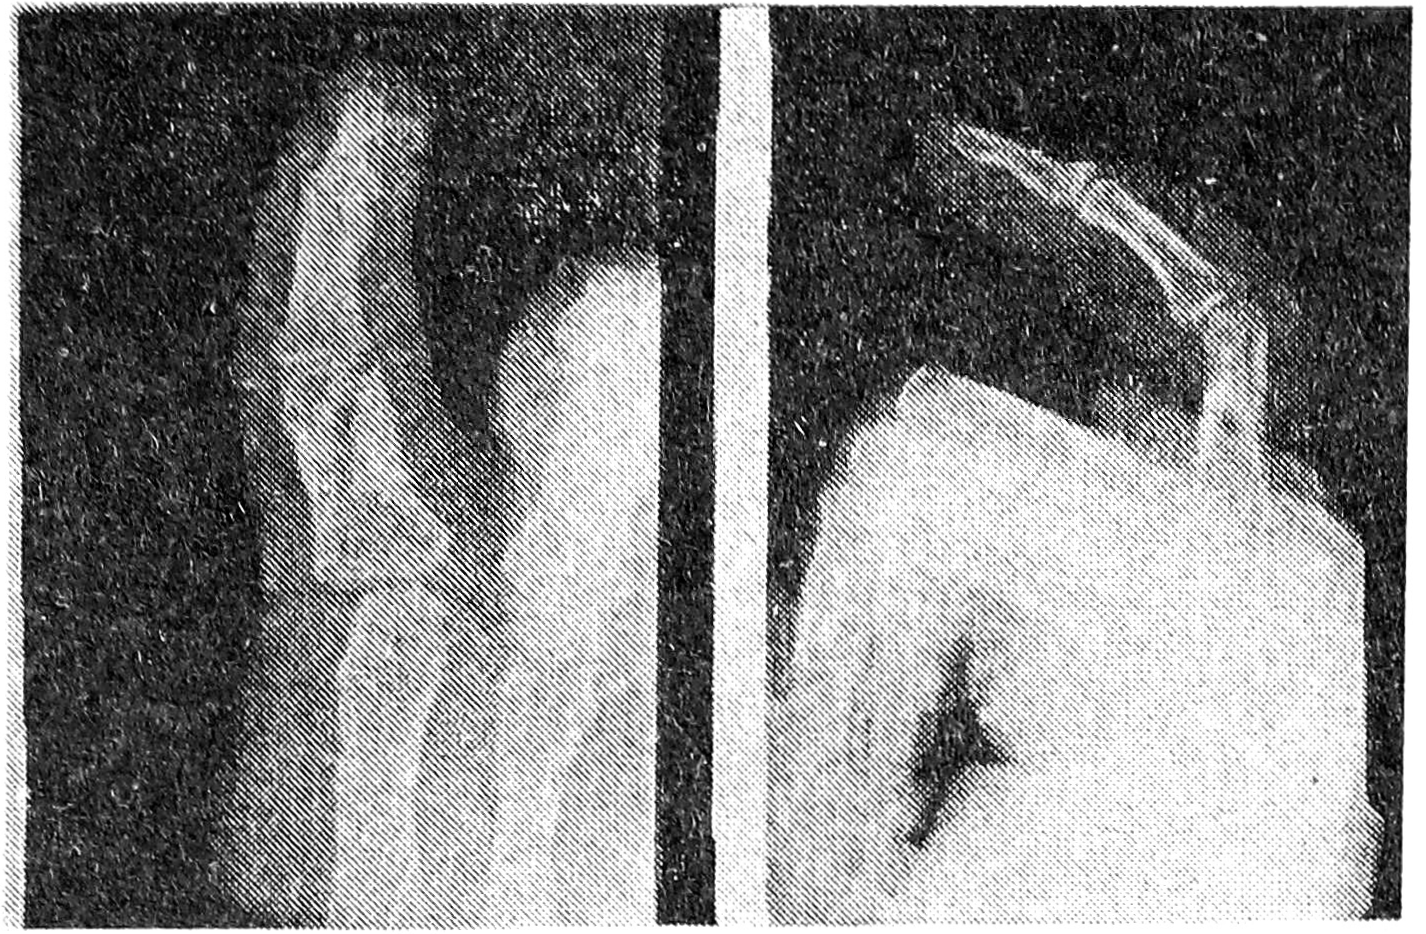

06.04.1994 г. была выполнена операция — щадящий артролиз проксимального межфалангового сустава V пальца левой кисти по описанному методу (рис. 2). Кожные швы были сняты через 12 дней. Получил курс физиомеханолечения. Через 3 недели после операции объем движений в оперированном суставе полностью восстановился.

Рис. 2. Рентгенограмма в прямой и боковой проекциях того же больного после щадящего артролиза проксимального межфалангового сустава V пальца левой кисти.